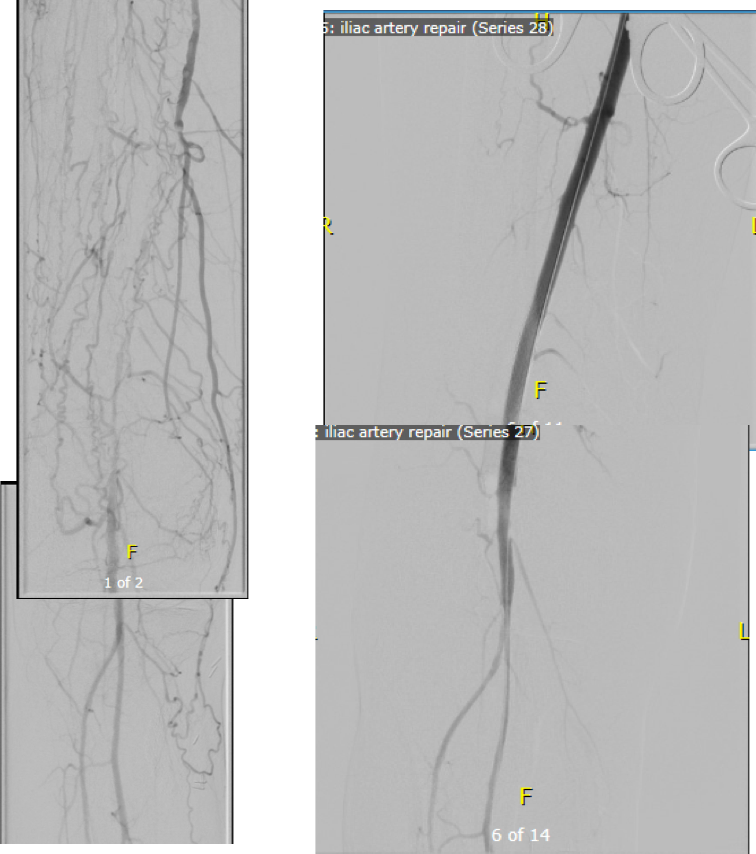

I contacted LeMaitre Vascular and got in touch with your representative, L. Fisher, who promptly sent the Moll Ring Cutters I needed to perform a remote endarterectomy of the patient’s occlusive external iliac and superficial femoral artery plaque. The technical details of remote endarterectomy are have been covered in my blog (https://vascsurg.me/?s=endore), but in the end, through a 7cm incision in the groin (don’t believe the hype, this is minimally invasive), I restored his arteries to their original open condition. Shown below are the results. It was with great sadness that I heard that the LeMaitre Vascular equipment being sent were the last of the stock available in North America. The patient did very well, with the operation completed well before lunch, and is recovering rapidly from his small wound and big rescue. He gets to walk out of the hospital on two legs, but also with the surety that he avoided a major bypass operation, and avoided the short term gains of stenting from the aorta to the profunda -more peel packs and landfill items and a dubious long term durability. Hey, I even used a XenoSure patch on the common femoral.